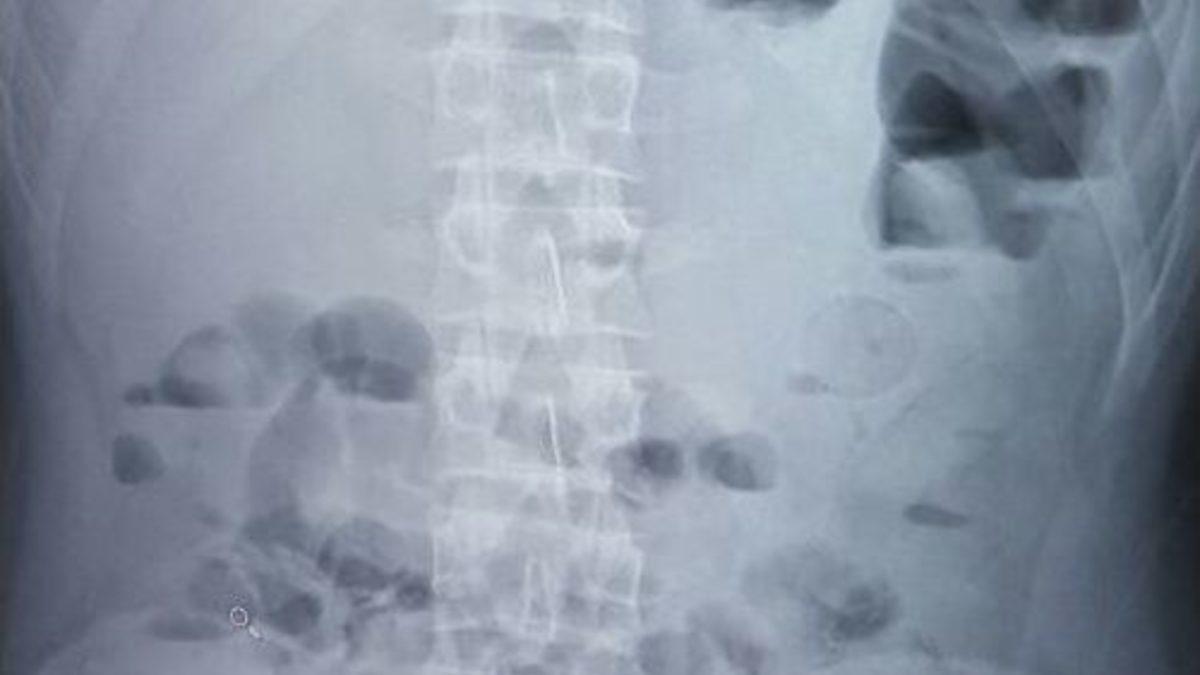

Yozgat’ta bir Afgan’ın midesinde prezervatif içerisine saklanmış 1 kilo 37 gram eroin ele geçirildi.Edinilen bilgilere göre, Yozgat Emniyet Müdürlüğü Uyuşturucuyla Mücadele Şube ekipleri tarafından yapılan yol uygulamasında durdurulan yolcu otobüsünde yabancı uyruklu şahıs üzerinde yapılan aramada, montunun iç cebinde siyah renkli poşet içerisinde 7 adet prezervatife preslenmiş olarak sarılı vaziyette uyuşturucu ele geçirildi.Üzerinde kimliği bulunmayan ve kendisinin Afgan uyruklu olduğunu beyan eden şahısın bitkin hali ve şüpheli davranışları dikkat çekti. Şahsın ağırlarının bulunduğunu söylemesi üzerine vücudunda başka uyuşturucu madde olabileceğinden şüphelenen polis şahsı hastaneye götürdü.Hastanede çekilen röntgen filminde, midesinde ve bağırsaklarında yabancı cisim olduğu tespit edildi.Hastanede 2 gün süreyle tutulan şahsın tuvalet ihtiyacını gidermesi sonucu 61 adet prezervatife preslenmiş toplamda 1 kilo 37 gram eroin maddesi ele geçirildi.Daha sonra şahıs adliyeye sevk edildi.